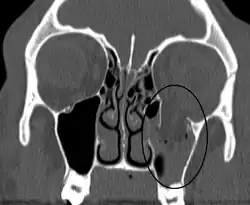

An orbital blowout fracture of the floor of the left orbit. | |

Thin cut (2-3mm) CT scan with axial and coronal view is the optimal study of choice for orbital fractures.[16][17]